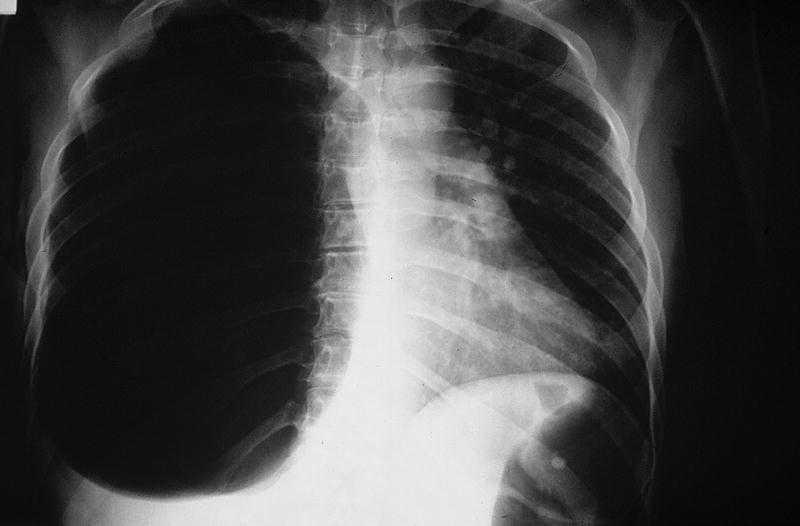

Manejo de neumotórax a tensión

El neumotórax por tensión es una condición en la cual hay una acumulación progresiva de aire en el espacio pleural, que es el espacio entre los pulmones y la pared…